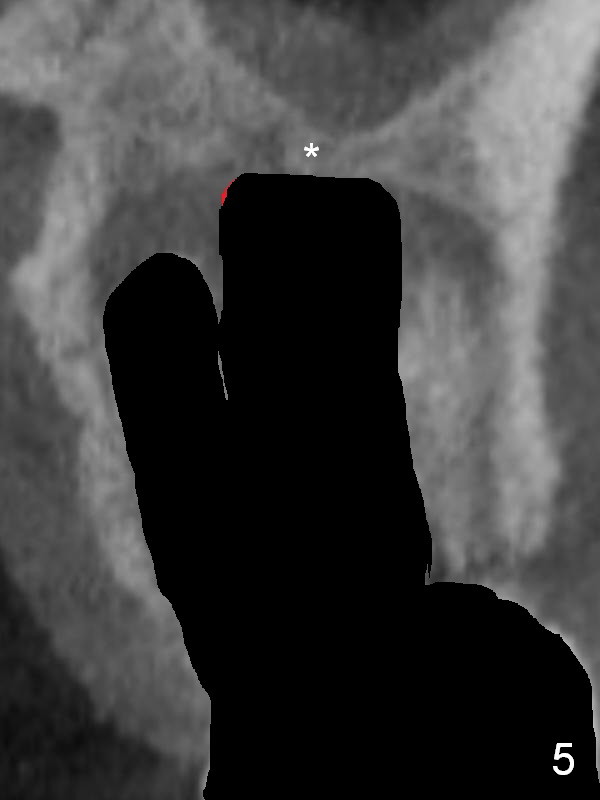

There is purulent discharge from the mesiobuccal fistula (Fig.1 <) during the tooth #14 extraction. Fig.2 is a coronal section of CBCT of the affected tooth showing a large apical lesion (*). When the tooth is removed (Fig.3), limited amount of granulation tissue is removed apical to the palatal root (P in Fig.2). The granulation tissue (Fig.4 red area) above the septum (Fig.3 S) is thoroughly extirpated when the septum is removed (Fig.5 black area).

The septum perforates into the distobuccal socket when 4.3 mm drill is being used. The sinus floor bone (Fig.5 *, Fig.6-8 red dashed line) has to be used for primary stability. Finally a 6x20 mm tap achieves stability apparently by engaging to the mesial and distal walls of the socket (Fig.6). The insertion torque of a 6x20 mm tissue-level implant is > 60 Ncm (Fig.7) with allograft packed into the remaining socket (*).